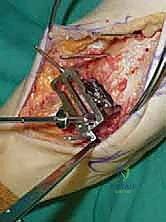

3. إزالة النتوءات العظمية وتحضير المفصل (Debridement)

بمجرد كشف المفصل، يقوم الجراح بإزالة الغشاء الزلالي الملتهب والزوائد العظمية (Osteophytes) التي تعيق الحركة. هذه الخطوة ضرورية لاستعادة المعالم التشريحية الطبيعية قبل إجراء القطع العظمي.

5. القطع العظمي الظنبوبي (Tibial Bone Cut)

باستخدام منشار جراحي دقيق التذبذب، يتم إزالة شريحة رقيقة جداً (بضعة مليمترات) من السطح السفلي التالف لعظمة الظنبوب. يتم القطع بحذر شديد لتجنب إصابة الأوتار الخلفية أو الأوعية الدموية.

6. القطع العظمي الكاحلي (Talar Bone Cut)

بشكل مشابه، يتم توجيه دليل القطع نحو عظمة الكاحل (Talus) وإزالة السطح الغضروفي التالف وت